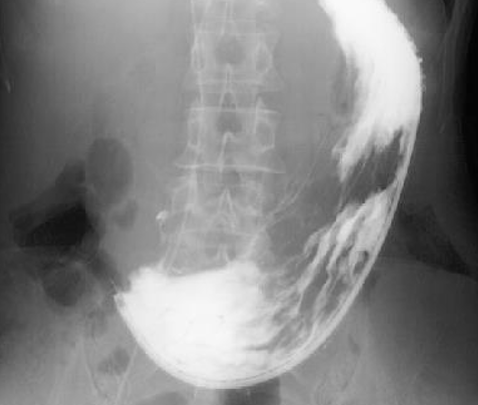

Describe the typical presentation of someone with oesophageal carcinoma

See example:

Describe the typical presentation of someone with gastric cancer